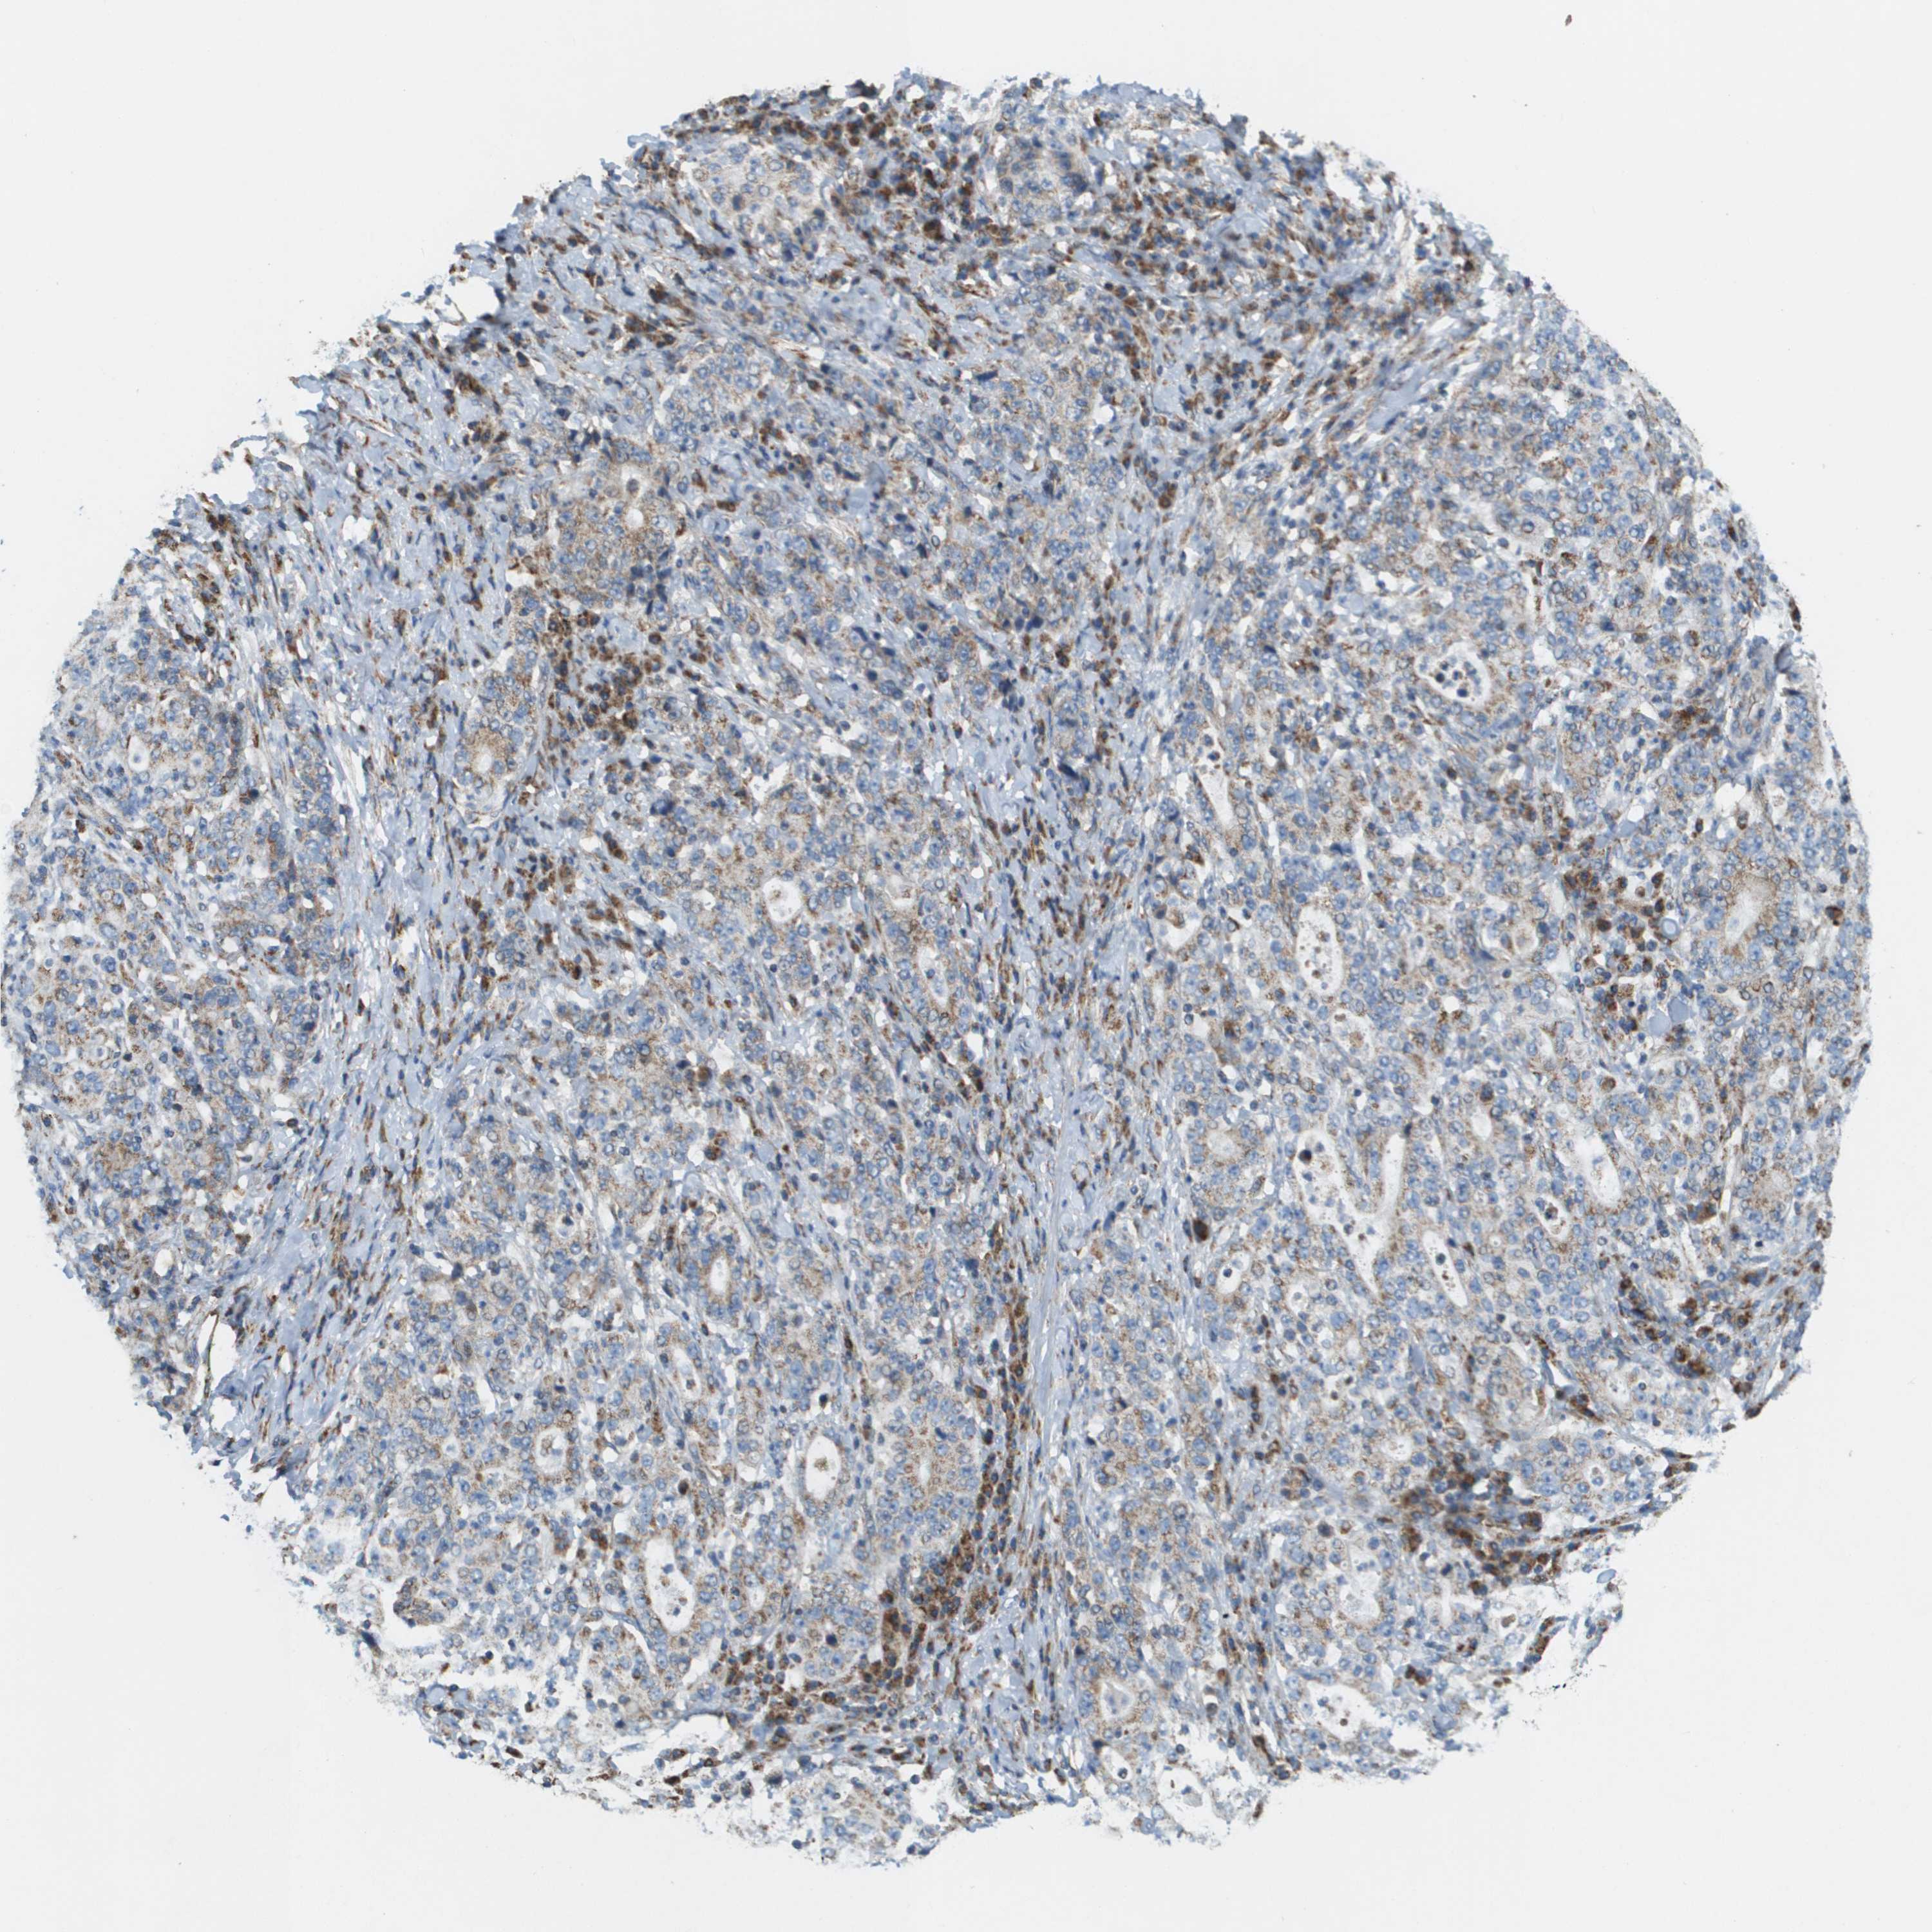

STOMACH CANCER - Protein expressioni

A mouse-over function shows sample information and annotation data. Click on an image to view it in a full screen mode. Samples can be filtered based on level of antibody staining by selecting one or several of the following categories: high, medium, low and not detected. The assay and annotation is described here.

Note that samples used for immunohistochemistry by the Human Protein Atlas do not correspond to samples in the TCGA dataset.

Antibody stainingi

Antibody staining in the annotated cell types in the current human tissue is reported as not detected, low, medium, or high, based on conventional immunohistochemistry profiling in selected tissues. This score is based on the combination of the staining intensity and fraction of stained cells.

Each image is clickable and will lead to virtual microscopy that enables deeper exploration of all samples and also displays staining intensity scores, fraction scores and subcellular localization as well as patient and tissue information for each sample.

Antibody HPA017238

Staining

High

Medium

Low

Not detected

Intensity

Strong

Moderate

Weak

Negative

Quantity

>75%

75%-25%

<25%

None

Location

Nuclear

Cytoplasmic/membranous

Cytoplasmic/membranous,nuclear

Adenocarcinoma, NOS